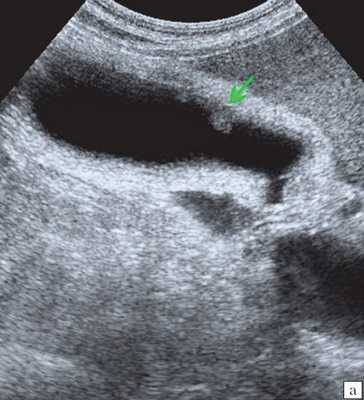

Узкая ножка визуализировалась у 85 % пациентов, широкое основание - у 15 %. Иногда можно было выявить эхографический симптом "пламени свечи", при этом наблюдалось дрожание полипа. Такой феномен имел место при наличии полипов небольших размеров и вытянутой формы и свидетельствовал об их тонкой ножке. Холестерозные полиповидные выросты размерами 2-4 мм исходили как бы непосредственно из-под слизистого слоя и имели широкое основание. В нашей выборке все холестериновые полипы больших размеров (16-22 мм) имели тонкие ножки, хотя в части случаев эхографически создавалось впечатление о наличии широкого основания (рис. 1).

а) Полип размером 22 мм, с фестончатыми контурами, пониженной эхогенности, ложноположительная диагностика широкого основания из-за ограниченной смещаемости в просвете желчного пузыря.

Ультрасонография является эффективным средством выявления полиповидной формы холестероза 9. Традиционной считается следующая сонографическая характеристика холестериновых полипов: неподвижные гиперэхогенные структуры, которые не дают акустической тени и прикрепляются к стенке желчного пузыря. Контуры таких образований, как правило, ровные, а размеры таких образований различны, чаще не превышают 10 мм (рис. 2).

a) Одиночный полип в желчном пузыре (гиперэхогенное пристеночное неподвижное образование, с ровными контурами, без акустической тени).

Однако, по некоторым данным, размеры холестериновых полипов могут быть более 20 мм. Кроме того, полипы больших размеров (в 7% от общего числа) могут иметь пониженную эхогенность и фестончатый контур.

Мелкие холестериновые включения, образующие диффузную сеточку в толще подслизистого слоя размерами 1-2 мм, выглядят как локальное утолщение или уплотнение стенки желчного пузыря и в некоторых случаях (см. рис. 2) вызывают реверберацию (эхографический симптом "хвост кометы").

Характер ножки полипа традиционно учитывается в онкологической практике как признак, ассоциированный со злокачественной природой образования. Вероятность возможной малигнизации больше, если у него имеется широкое основание, а не тонкая ножка. Однако необходимо принимать во внимание возможность ложноположительной диагностики широкого основания при полипах больших размеров из-за их ограниченной смещаемости в просвете желчного пузыря. Дрожание, напоминающее пламя свечи, наблюдается у полипов небольших размеров и вытянутой формы, и указывает на их тонкую ножку 9.